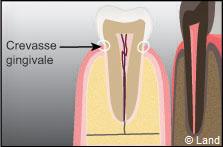

L’objectif des soins d’hygiène dentaire est l’élimination de la plaque dentaire dans le but de contrôler le nombre de bactéries buccales. En effet, ce sont principalement ces bactéries qui sont responsables des maladies bucco-dentaires qui atteignent les dents (caries) ou les gencives (maladies parodontales).